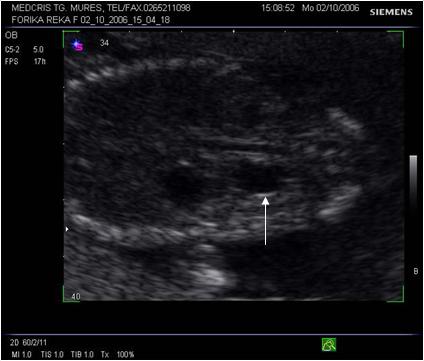

Fig. nr. 258. Defectul de inchidere a arcurilor vertebrale din figura anterioara, prezentat in sectiune transversala.( Sageta )

Fig. nr. 273. Dilatatie pielocaliceala renala fetala, unilaterala, la 16 sapt.( sageata)